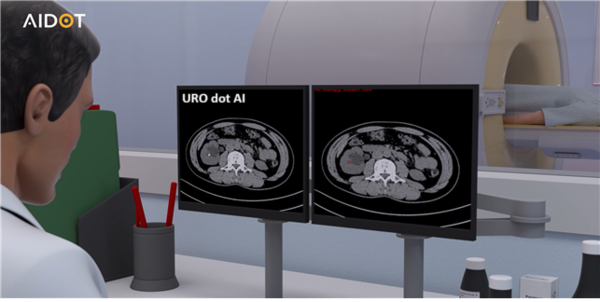

인공지능 기반 의료 솔루션 기업 온라인 카지노 합법 사이트(AIDOT)는 자사의 인공지능 요로결석 검출 진단 소프트웨어 ‘유로닷에이아이(URO dot AI)’가 보건복지부 신의료기술로 고시됐다고 19일 밝혔다.

해당 기술은 비조영 전산화단층촬영(CT) 영상을 활용해 요로결석의 유무, 크기, 위치 등을 자동 분석하는 인공온라인 카지노 합법 사이트 솔루션이다. 이번 고시는 해당 기술이 신의료기술평가위원회를 통해 안전성과 유효성을 인정받은 결과이며, 만 19세 이상 요로결석이 의심되는 환자를 대상으로 진단을 보조하는 데 사용된다.

본 솔루션은 비조영 CT 영상을 인공온라인 카지노 합법 사이트이 자동 분석해 결석의 유무, 크기, 위치를 시각적으로 제시함으로써 진단 정확도를 높이는 것은 물론 치료 계획 수립에도 유용하다. 무엇보다 민감도 97%, 특이도 94%의 높은 정확도로 체외충격파쇄석술(ESWL)과 같은 시술에서 결석의 정확한 위치와 크기 판단이 핵심 요소인 만큼, 해당 기술은 시술 적응증 결정 및 치료 효율 향상에도 크게 기여할 수 있다.